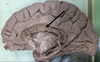

1. Identify 2 2. Identify 3 3. Identify 4 4. Identify 5 5. Identify 6

1. Falx Cerebri 2. Corpus callosum 3. Midbrain 4. cerebellum, grey matter 5. basilar artery

128

1. Name the dural venous sinuses related to number 2 2. Name the parts of number 3 3. Name the grey matter mass present in the white matter of structure 5

1. Superior and inferior saggital, straight sinus. 2. Rostrum, genu, trunk/body and spleenium 3. cerebellar nuclei

129

1. Identify 3 2. Identify 4 3. Identify 5 4. Identify 6 5. Identify 7 6. Identify 8 7. Identify 9 8. Identify 10 9. Identify 11 10. Identify 12

1. Dura Mater 2. Falx cerebri 3. Corpus callosum 4. Septum Pellucidum 5. Fornix (hippo to mamillary bodies) 6. Interthalmic adhesion 7. midbrain 8. Straight sinus 9. internal carotid 10. Tentorium cerebelli

130

1. Name the dural venous sinuses related to 4 2. Name the dural venous sinuses related to 12 3. How does 10 terminate

1. superior and inferior saggital, straight sinus 2. sigmoid, Transverse and superior petrosal sinuses 3. Great Vein of Galen